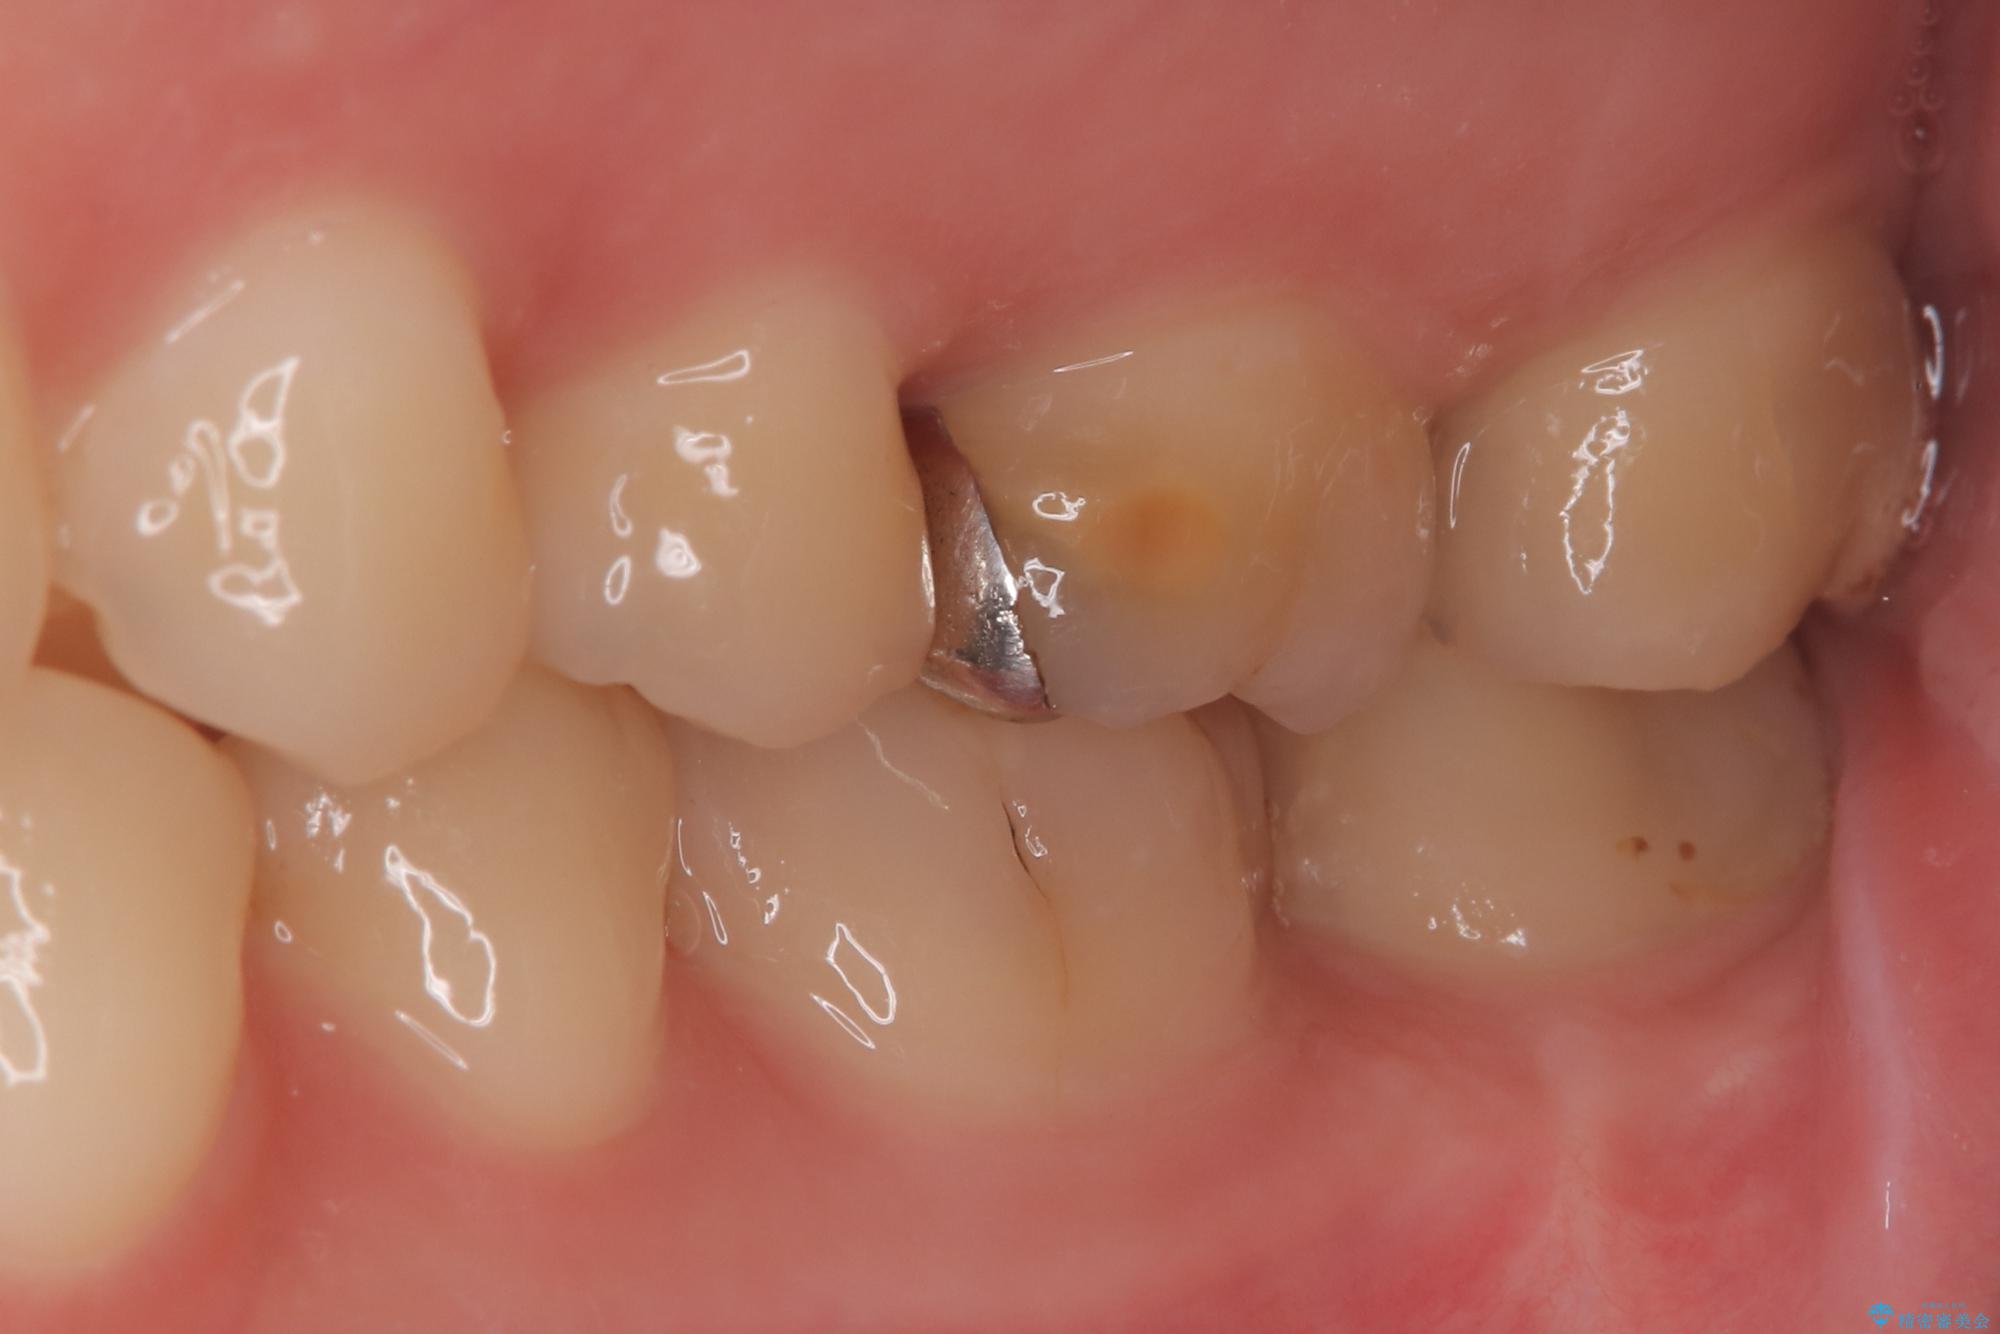

- 「冷たいものが強くしみる」という主訴でご来院されました。精密な診査の結果、虫歯が非常に深く、通常であれば神経を全て抜く「抜髄(ばつずい)」が必要な状態でした。しかし、神経を抜くと歯の寿命が縮まってしまうため、今回は神経の一部を温存する**「部分的断髄法(VPT)」**を提案しました。高い殺菌性と封鎖性、そして組織の再生を促す効果を持つMTAセメントを使用して神経を保護し、最終的には強度と審美性に優れたセラミックで修復する計画を立案しました。

部分的断髄法(MTAの使用): ラバーダム防湿を行い、無菌的な環境下で虫歯を慎重に除去。神経の露出を確認した後、炎症を起こしている一部の神経のみを除去し、残りの健全な神経を保護するためにMTAセメントを充填しました。これにより、神経の機能を維持し、歯を内部から守ることが可能となりました。